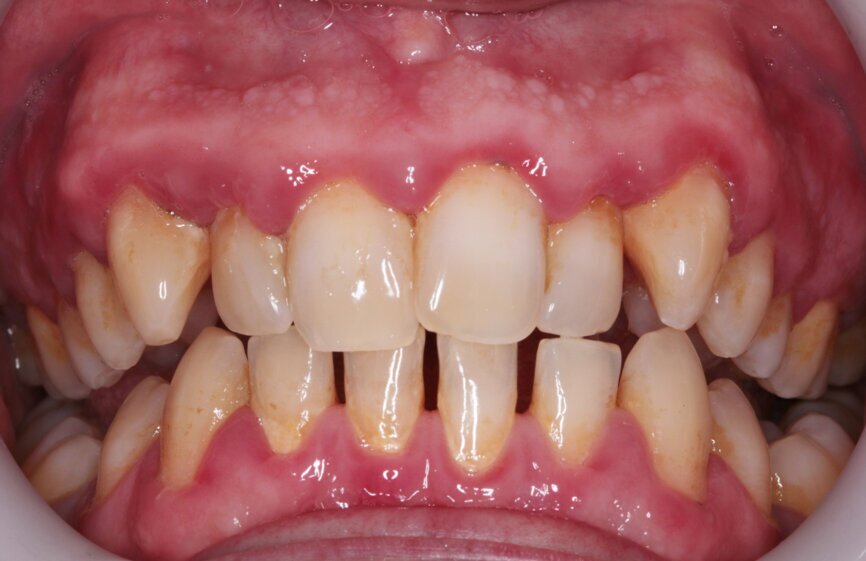

Outcome

While the patient arrived with misaligned teeth that were difficult to clean and gingivae that reflected this, he left with clean, light teeth, pink gingivae and a much straighter smile. He was very pleased and expressed warm gratitude for his treatment. He practised every bit of advice given with conspicuous diligence and as a result he reaped the rewards.

I was even happy with this having been a compromised case. Of course, a comprehensive orthodontic treatment plan would have intruded the central incisors, de-rotated the canines further and closed the mandibular spaces, but this is not what the patient wanted. His molar relationships did not change, but we affordably and conservatively made his visible teeth straighter, whiter and easier to clean, and to me this is the very essence of what GDP orthodontics is.

Fig. 7: Post-scaling anterior view

Fig. 14: Post-treatment 1

Fig. 15: Post-treatment smile

Fig. 16: Post-treatment anterior view